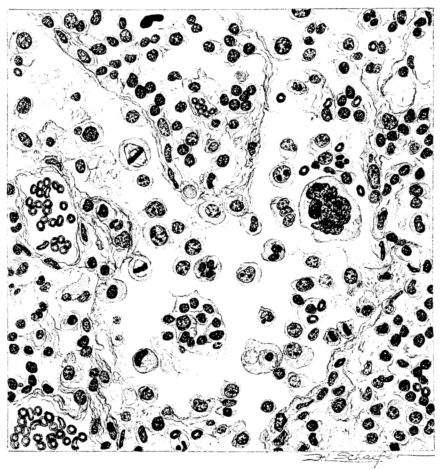

No matter what the portion of the lung from which the sections are derived, the fundamental changes found are the same. The subpleural sheets are spread wide apart, now by empty spaces, now by coagulated fluid. The process extends from the surface through the interlobular septa (Fig. XX), and is accentuated where the connective tissue is more prominent around vessels and bronchi. The nature of the infiltrate in the subpleural and interstitial tissues becomes more evident in the alveoli, which likewise are filled. The material varies somewhat in appearance, probably dependent upon its proteid content. Not infrequently the alveoli contain a homogeneous, pink-staining mass, which resembles the colloid of the thyroid gland. Again, it may be simply a coarse granular precipitate (Fig. XXIII), and in still other instances, small sticks and strands form the bulk of the alveolar content (47, 92, 140, 156). This subpleural, interstitial, perivascular, peribronchial, and alveolar edema, which is a term applicable to this collection of fluid, is very prominent, and although its intensity varies in different portions of the lung; and although it may be replaced in some areas by other types of exudate, unquestionably, this is the dominating expression of the inflammatory process in the early stage of the disease.

As might be expected from the gross appearance, the alveoli vary in size. At times slightly collapsed and at other times overdistended, their lumina are still the seat of the inflammatory exudate, although the mechanical change may allow of some variation in the appearance of their walls. As a rule, however, the alveolar wall is prominent and owes its conspicuousness to the tortuous, engorged vessels within. These vessels contain red blood cells almost exclusively, and on account of the partial, occasionally complete, loss of the lining epithelium, the alveolar wall appears as a huge, dilated arteriole (101) separating the lakes of coagulated material in the spaces (Fig. XXIII). There are areas, as indicated above, where the alveolar content may be more definitely arranged in the form of beaded or homogeneous strands of different caliber; the smallest resemble delicate threads. They tend to converge toward the alveolar wall like wheat in a sheaf, and often pass through this wall by way of the so-called pores of Cohn; as soon as the body of the neighboring alveolus is reached, they again present a fan-like expansion into innumerable, fine strands (Fig. XXII). Where the exudate is more fibrinous, the alveolar wall is less likely to be distended, its vessels are not so prominent, and their content of red blood cells is definitely decreased. Still this is not the most extreme type of alveolar exudate met with at this stage. Perhaps, the most striking, although not the most frequent, exudate has a superficial resemblance to a huge, red blood clot, and it may be difficult to make out the alveolar walls separating the masses of well preserved red blood cells that fill the alveolar spaces. These areas are indistinguishable from infarcts and may be associated with thrombotic arteritis in near-by pulmonary vessels (47) (Figs. XXIV and XXV). Among the red blood cells an occasional strand of fibrin, a desquamated alveolar epithelial cell, and rarely a polymorphonuclear leucocyte may be encountered. The alveolar wall itself varies in the definition of its outline. When its vessels are greatly distended, when its alveolar epithelium is gone, and when its content consists largely of red blood cells, it is difficult to distinguish from the exudate which it encloses. However, when it is more compressed or when its epithelial lining cells are still more or less intact, it may be seen as a blue-staining strand under the low power of the microscope, for the well preserved nuclei lend it prominence.

21There are, of course, variations in the extent of the serum, the fibrin, and the hemorrhage in the exudate of the alveoli, and while these different types may occur as pure forms, often they are associated. In still other areas and varying in prominence, one finds as characteristic an exudate, not only of serum, strands of fibrin, and red blood cells, but also a diffuse dotting of the exudate with bacteria, singly, in pairs, clumps, and chains (92, 164) (Fig. XXI). This type of reaction is uncommon in pulmonary disease. It resembles more closely a streptococcus cellulitis such as is encountered frequently in the subcutaneous tissues, for example, a woody phlegmon, or a sero-hemorrhagic exudate like the avirile response to a rapidly fatal hemolytic streptococcus serositis. A similar reaction has been reproduced experimentally in animals which have been rendered aplastic with benzol previous to pulmonary insufflation, and it is conceivable that the lack of polymorphonuclear response in the inflammatory exudate may be associated with some such general destruction or temporary suspension of leucocytic formation (160).

A more striking picture, however, even than this aplastic alveolar exudate appears in the terminal bronchioles. In many instances, these are conspicuous on account of their size, for they are dilated to form prominent, often irregular, sacs (Fig. XV). The distention of these terminal bronchioles may be so great that the surrounding alveoli are compressed. What makes them even more conspicuous is their lining, once epithelium, but now a swollen, thick, homogeneously staining material, with complete loss of architecture; the material forms (with hematoxylin and eosin) a red band limiting the lung tissue and sharply demarcating it from the exudate within the bronchioles (48, 92). However, this ribbon of red, often thickened by fibrin deposition, is not always pure, for bacteria thrive in the dead tissue. They occur singly, paired, in chains, and also as circumscribed, dense masses which in size and position, simulate nuclei (162) (Fig. XVI). This same hyalinization of the epithelium, it will be recalled, occurs in the larger bronchi (Fig. V), and there, too, bacteria frequently develop in the dead tissue (Fig. VIII). In the smallest bronchiolar ramifications, acute epithelial necrosis is not infrequently encountered, even when the surrounding lung tissue is relatively normal (Fig. XVI). That the process does not stop with the epithelium, but, as in the larger bronchi, may extend through the entire structure of the bronchioles, is manifest. Even the alveolar walls may be involved and frequently homogeneous pink or red bands, now the phantom of the former viable lung tissue, mark the presence of the old wall of the alveolus (Fig. XVII). Occasionally, some architecture remains in this pink ribbon and then the involvement seems to be primarily in the vessels of the wall. Not all the vessels are involved, and next to a hyaline thrombus in one, there may be fresh blood, usually red blood, in its neighbor. The alveolar epithelium is usually denuded and thus accentuates the intensity of the change.